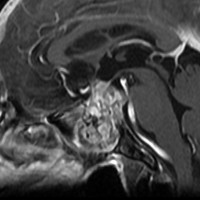

MRI T2強調画像(左)では等信号から高信号のまだらな境界が不明瞭な腫瘍が斜台から左海綿静脈洞内に浸潤しているのがみられます。T1強調ガドリニウム増強では,腫瘍がまだらに増強されています。トルコ鞍から鞍上部に伸び,視交差を侵し第3脳室底まで伸展しています。脊索腫が硬膜内に浸潤して神経組織と癒着することは珍しいことではありません。